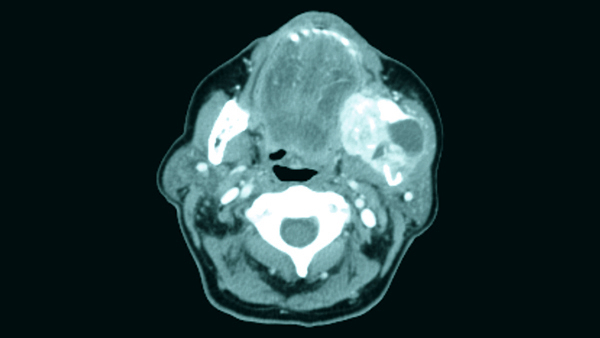

zystische Raumforderung am Hals rechts , axiale Schichtung CT.

V.a Laterale Halszyste